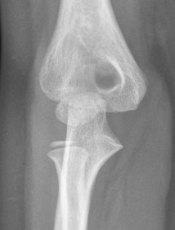

8 year old male: CRIT